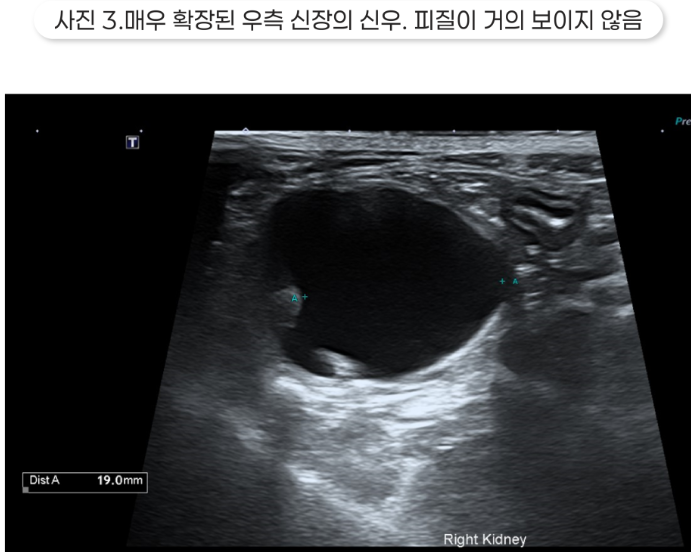

결석보다 가까운 쪽의 요관은 확장되어 있는데, 이는 요관 폐색을 의미합니다. 신우가 매우 확장되어 있었고, 특히 오른쪽 신장은 피질이 많이 얇아져 있고 심한 수신증 소견을 보였습니다.

수신증이 너무 심하면 해당 신장은 이미 기능을 상실했을 가능성이 높습니다.

다만 이 수술은 이미 기능하지 않는 신장에는 도움이 되지 않기 때문에, CT상에서 조영을 통한 우측 신장 기능 평가가 필요했습니다.

CT에서 정맥으로 조영제를 투여하면 일반적으로 1분 안에 신우에서 조영제가 보이는데, 조영제 투여 후 10분이 지나도 신우로 조영제가 나타나지 않아 신장 기능이 매우 떨어져 있음을 확인했습니다.

또 우측 신장에서는 아무리 기다려도 조영제가 아예 내려오지 않아 기능하지 않음을 확인했고, 때문에 우측 신장은 절제하고 좌측 신장에 SUB를 장착하기로 결정했습니다.